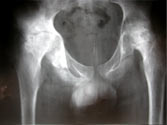

Fibrous ankylosis both hips post infection